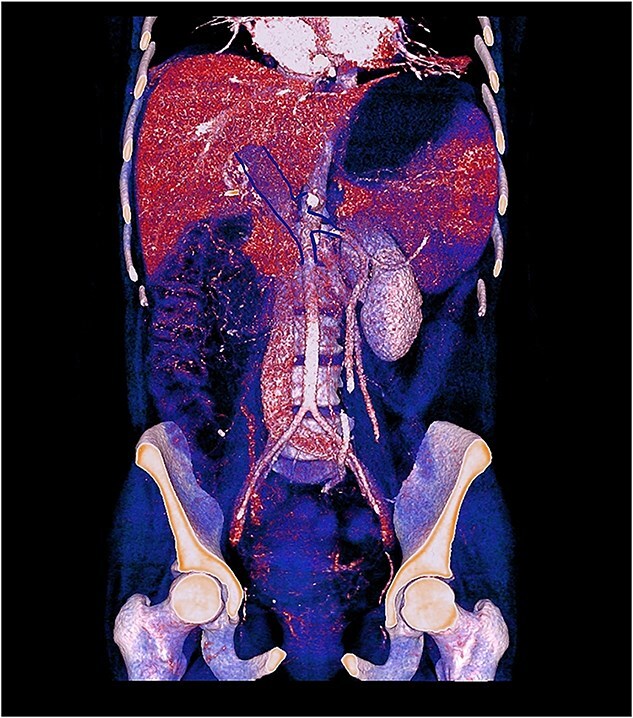

急性肠系膜静脉血栓形成是一种罕见且可能致命的肠道缺血原因。我们报告一个38岁的妇女异常子宫出血,与贫血,并长期使用醋酸甲孕酮。她表现出严重的腹痛、腹膜体征和全身炎症反应。计算机断层扫描显示门静脉、脾静脉和肠系膜上静脉血栓形成,空肠壁增厚。最初剖腹手术显示肠存活;开始全面抗凝。她后来出现穿孔,需要空肠切除术,随后再次手术治疗吻合口裂开。广泛的检查显示,除了使用黄体酮外,没有血栓前病变。本病例强调需要考虑激素制剂作为门-脾-肠系膜血栓形成的潜在触发因素,即使在没有合并症的年轻女性中也是如此,并需要寻求多学科、个性化的治疗,以平衡及时手术和保持肠道长度。

Acute mesenteric venous thrombosis is a rare and potentially lethal cause of intestinal ischemia. We report a 38-year-old woman with abnormal uterine bleeding, with anemia, and prolonged use of medroxyprogesterone acetate. She presented severe abdominal pain, peritoneal signs, and systemic inflammatory response. Computed tomography revealed thrombosis of the portal, splenic, and superior mesenteric veins with jejunal wall thickening. Initial laparotomy showed a viable bowel; full anticoagulation was started. She later developed perforation requiring jejunal resection and subsequent reoperation for anastomotic dehiscence. Extensive workup revealed no prothrombotic disorder other than progestin use. This case highlights the need to consider hormonal agents as potential triggers of porto-spleno-mesenteric thrombosis, even in young women without comorbidities, and to pursue multidisciplinary, individualized management to balance timely surgery with preservation of bowel length.